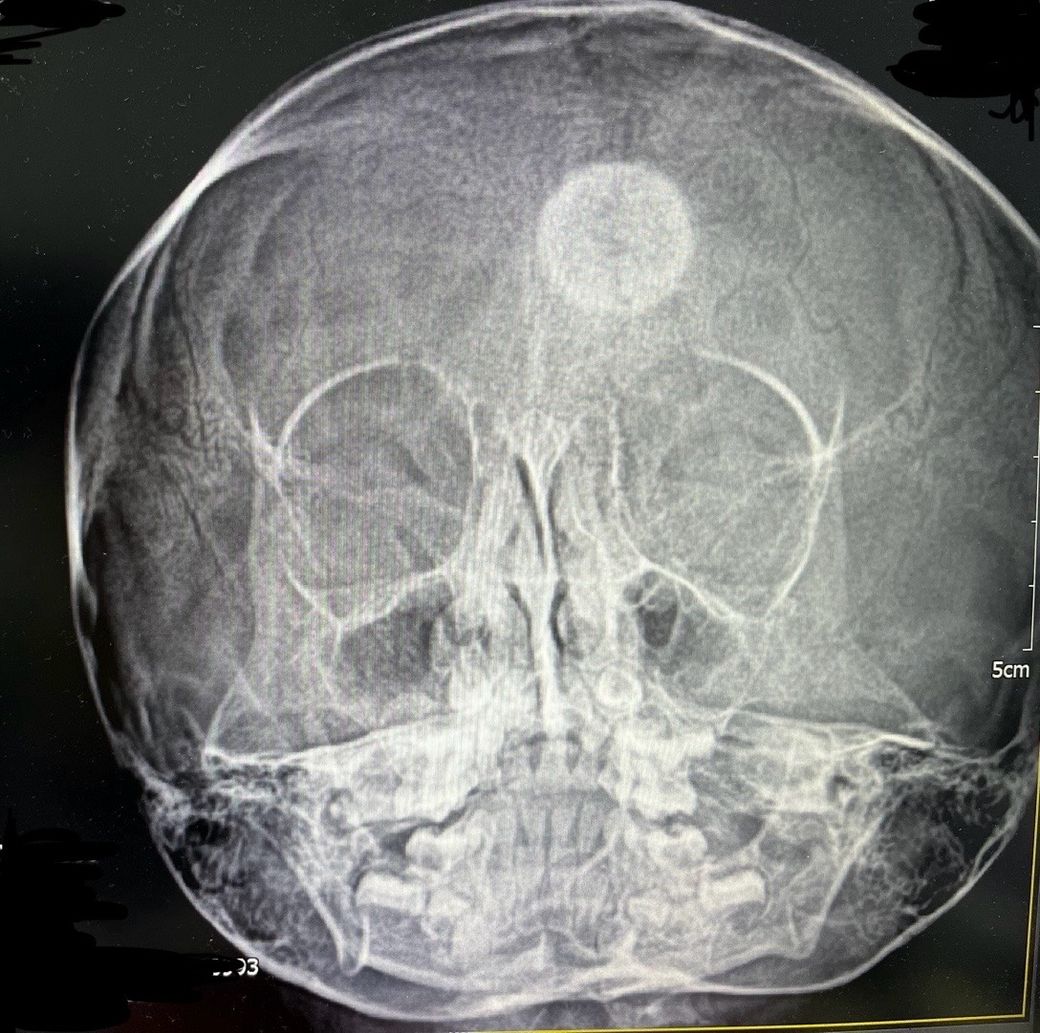

5세 여아입니다 얼마전 부비동 엑스레이사진 입니다

머리에 흰색 원이 보이는데요

소아과 원장님도 처음 보는거라시네요

무엇일까요?

진료 보려면 무슨과가 좋을까요?

• 2번 째 사진

아이의 X-ray 병변에 대해 걱정이신 듯합니다.

두개골 또는 뇌의 CT 검사가 필요할 것으로 생각됩니다.

CT 검사가 가능한 규모의 병원(종합병원 등)에 내원하셔서,

소아청소년과 또는 신경외과 의료진과 상의하시길 권장드립니다.

• 해당 소견과 관련하여서는 신경외과로 가셔서 보다 정밀한 검사를 받아보시는 것이 필요하겠습니다. 엑스레이 사진에서 분명 이상 소견이 있어 보이긴 하지만 해당 검사 소견만으로는 구체적으로 무슨 문제인지 파악 및 감별 가능하지 않습니다. 보다 자세하고 구체적으로 상태를 파악하고 어떻게 대처해야 하는지 등 여부에 대해서는 정밀 검사를 먼저 받은 이후에 판단을 받으시는 것이 필요하겠습니다.